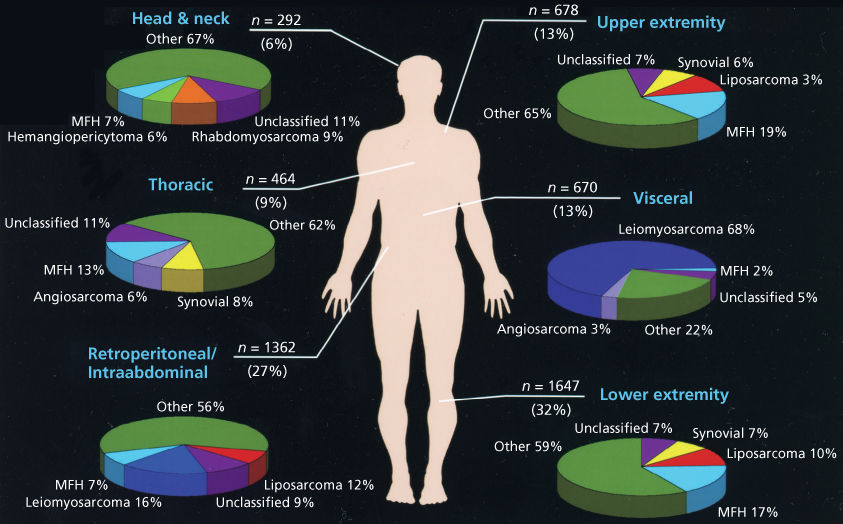

Soft Tissue Sarcoma Types Vrogue co

https://oncohemakey.com/wp-content/uploads/2017/04/image05971.jpeg